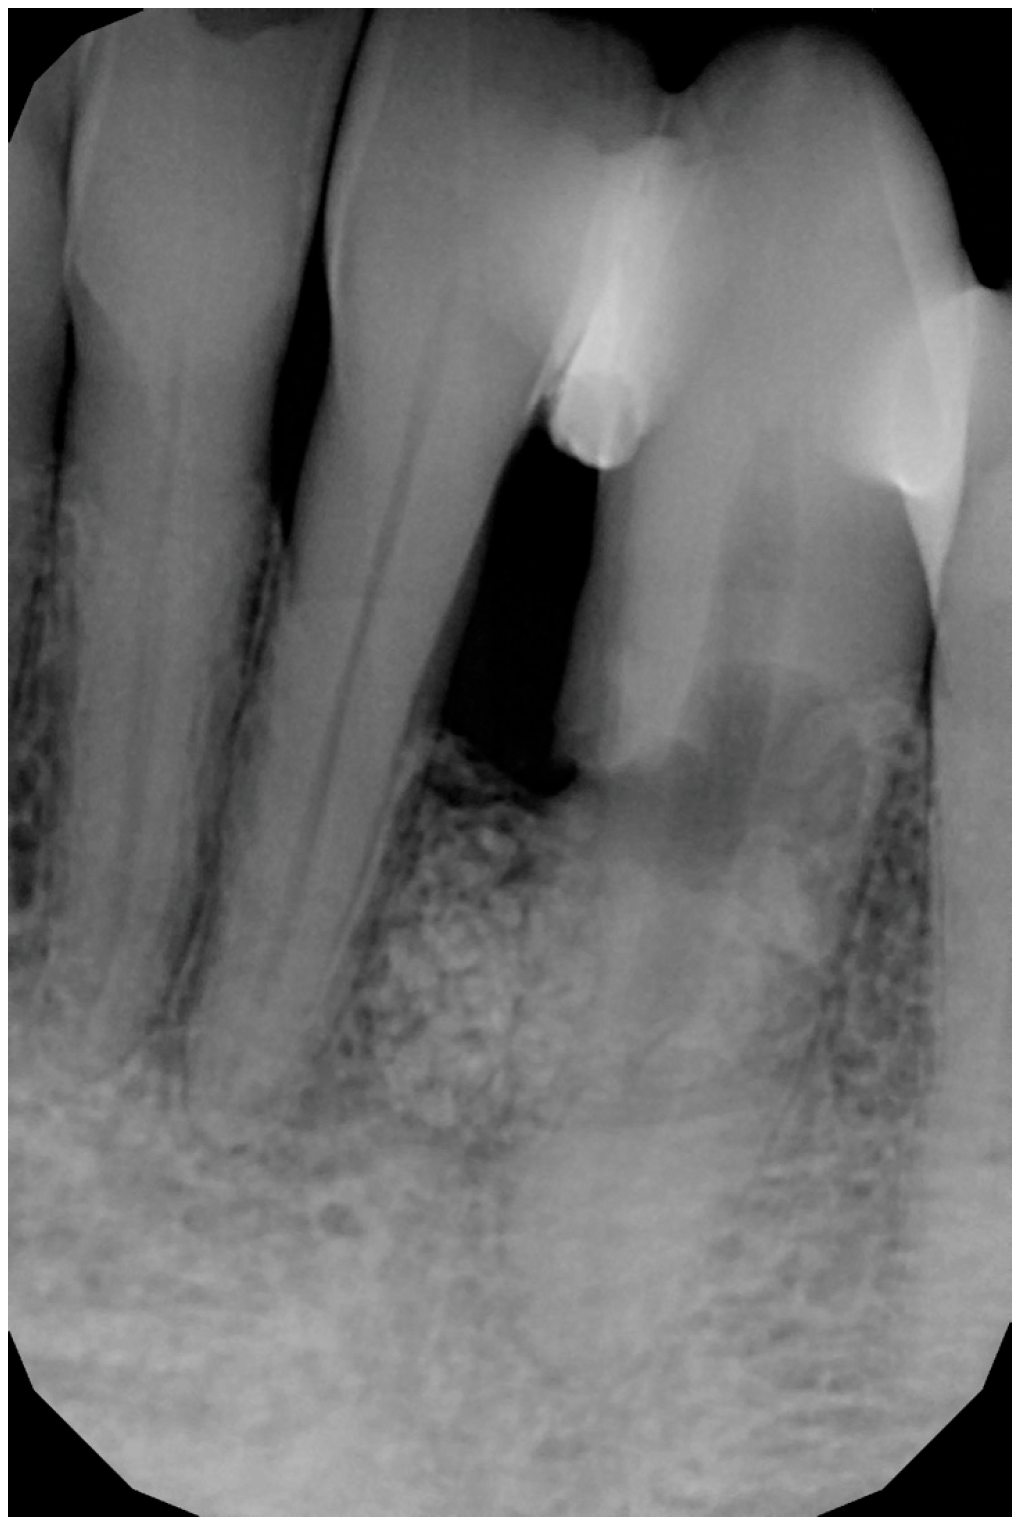

A 56-year-old male patient has been under our care for several years. The canine tooth in position 33 was treated 10 years ago using guided tissue regeneration (GTR) to address an infrabony defect. At that time, the biomaterial employed was an anorganic bovine bone-derived matrix (ABBM) in conjunction with a resorbable membrane. After 7 years, the tooth began to exhibit signs of internal root resorption and ultimately fractured (Figure 1).

The extraction was performed at another practice while the patient was away for work, and it was conducted on an emergency basis (Figure 2). Three months post-extraction, the patient returned to our clinic, reporting a severe bone defect with significant loss of both the mesial bone peak and the buccal plate (Figure 3, Figure 4 and Figure 5). The proposed plan, which the patient accepted, involved performing a regenerative procedure using an FCS followed by delayed implant rehabilitation.

Figure 1. Intraoral X-ray at baseline, highlighting the damaged root of element 33.

Figure 2. Intraoral radiograph following the extraction of the canine.